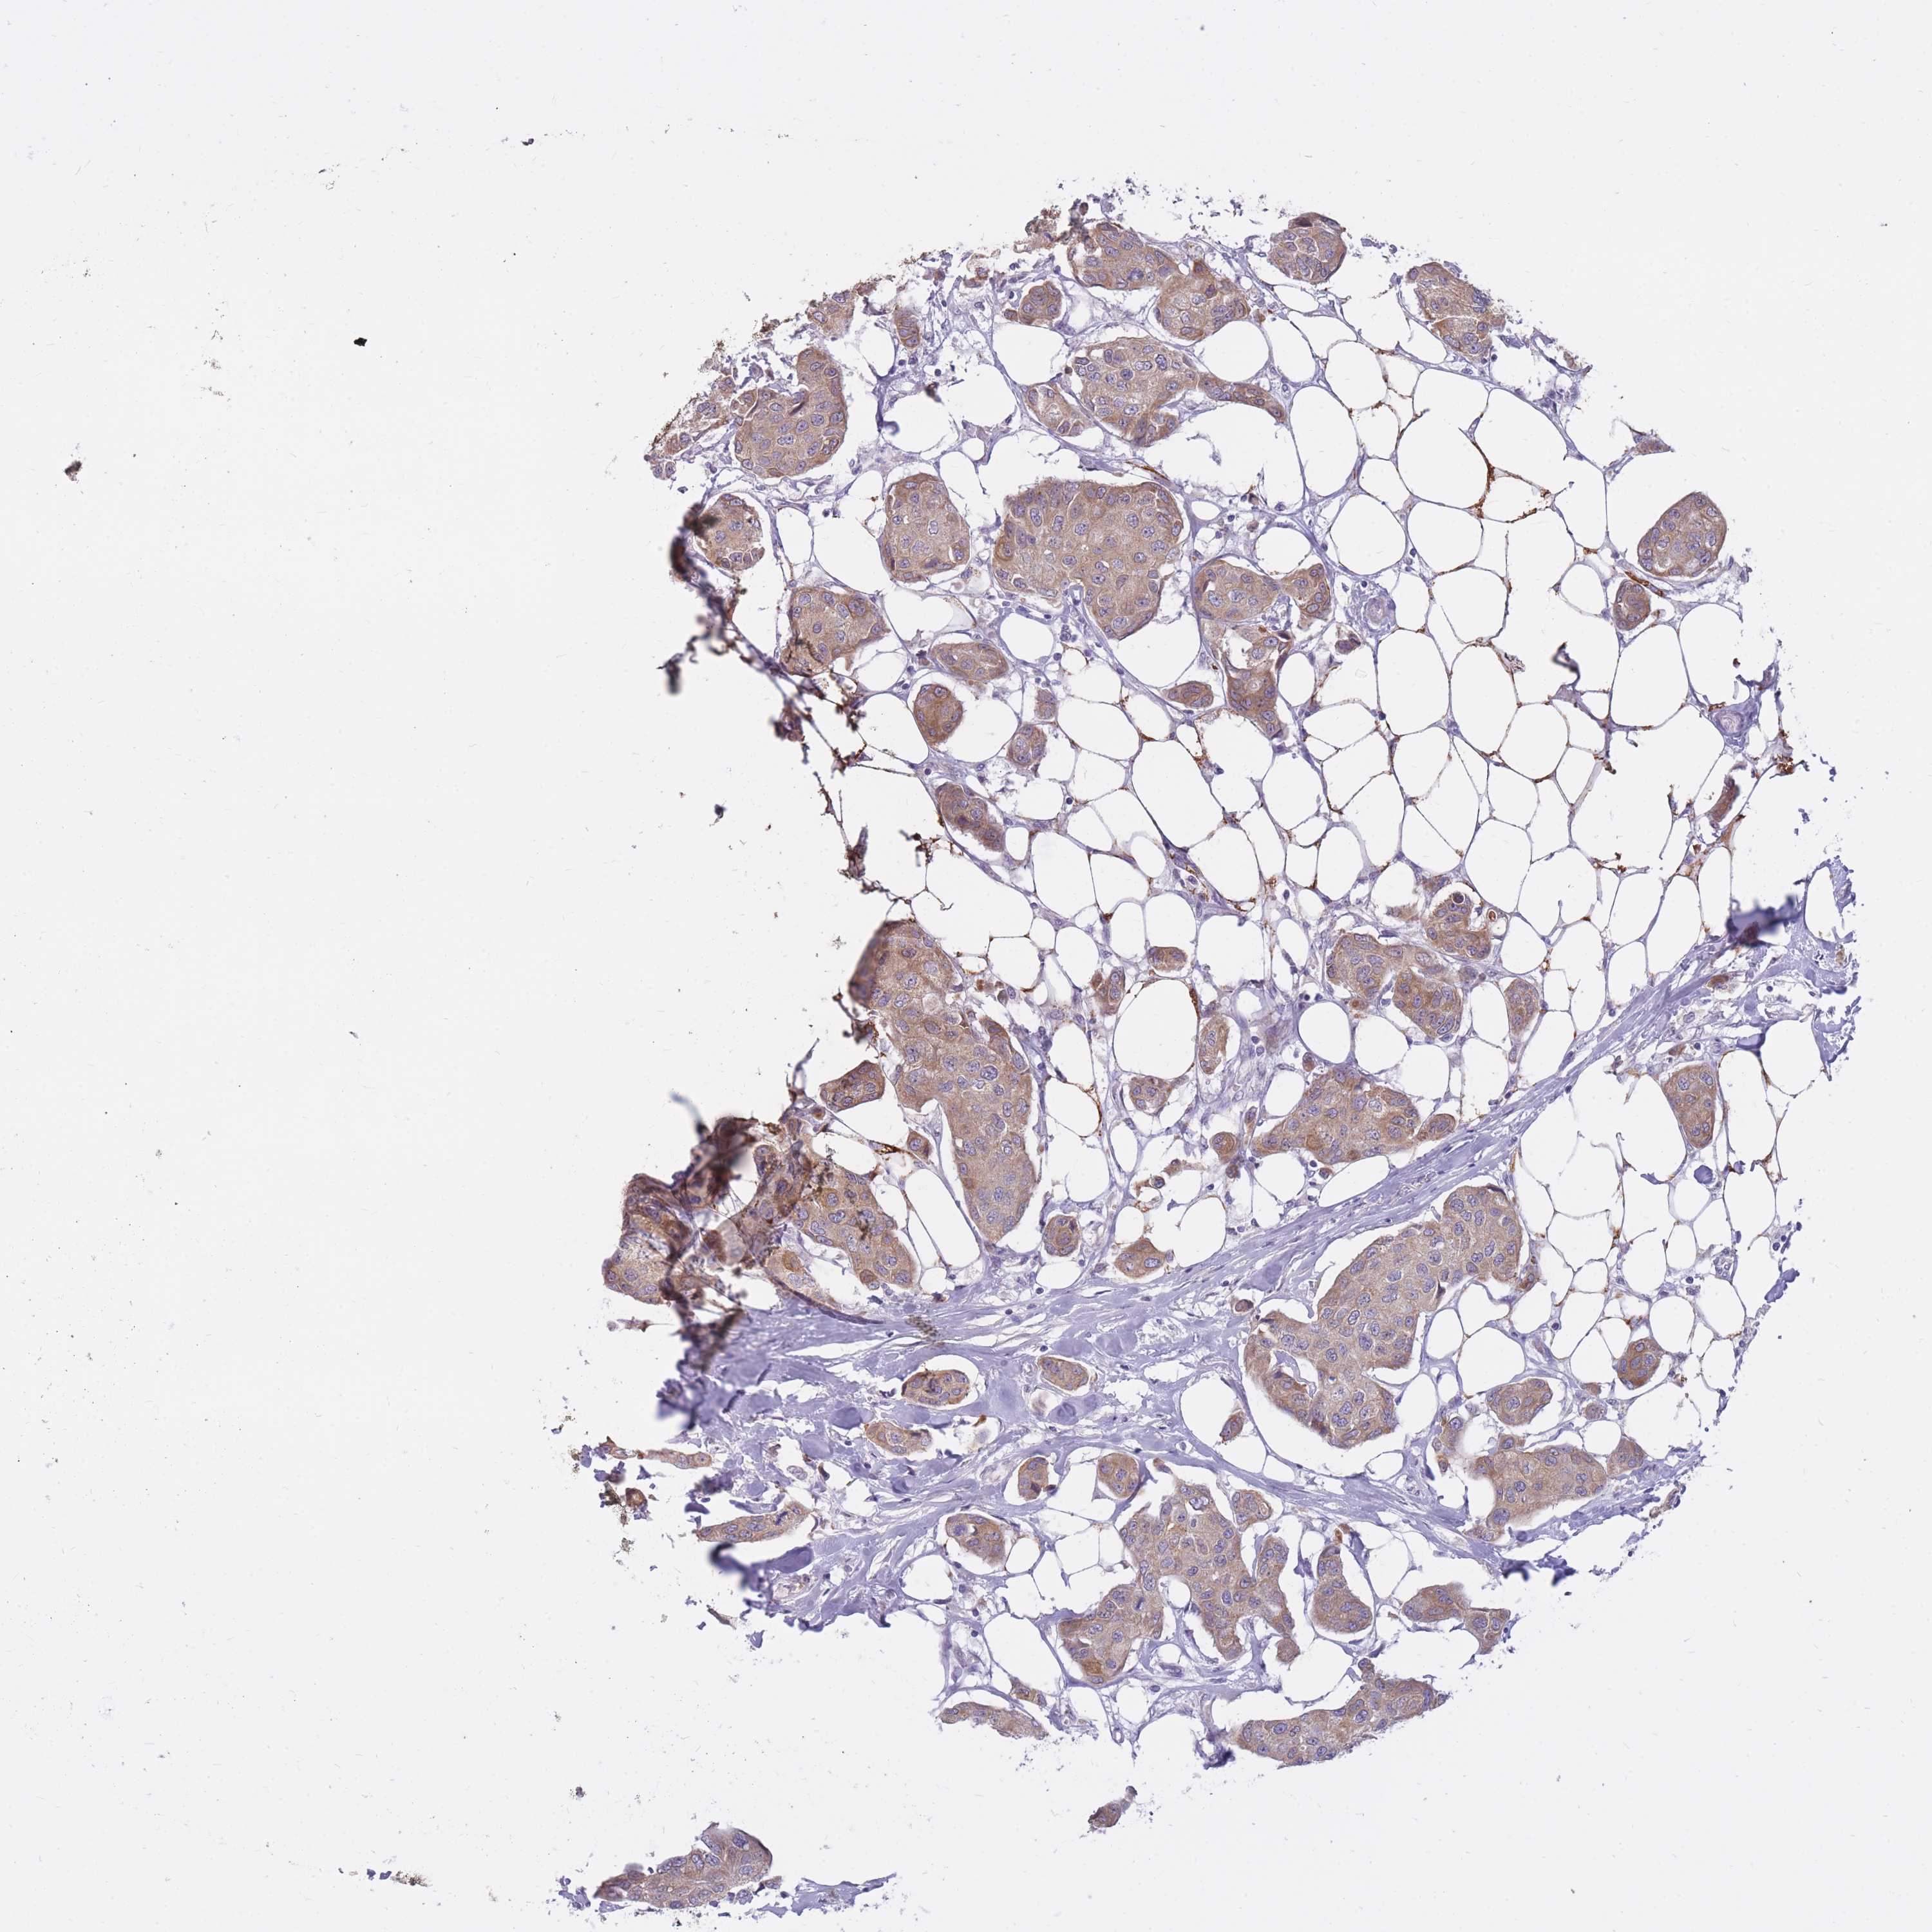

CANCER BREAST CANCER Show tissue menu

BRCA TCGA BRCA VALIDATION PROTEIN EXPRESSION